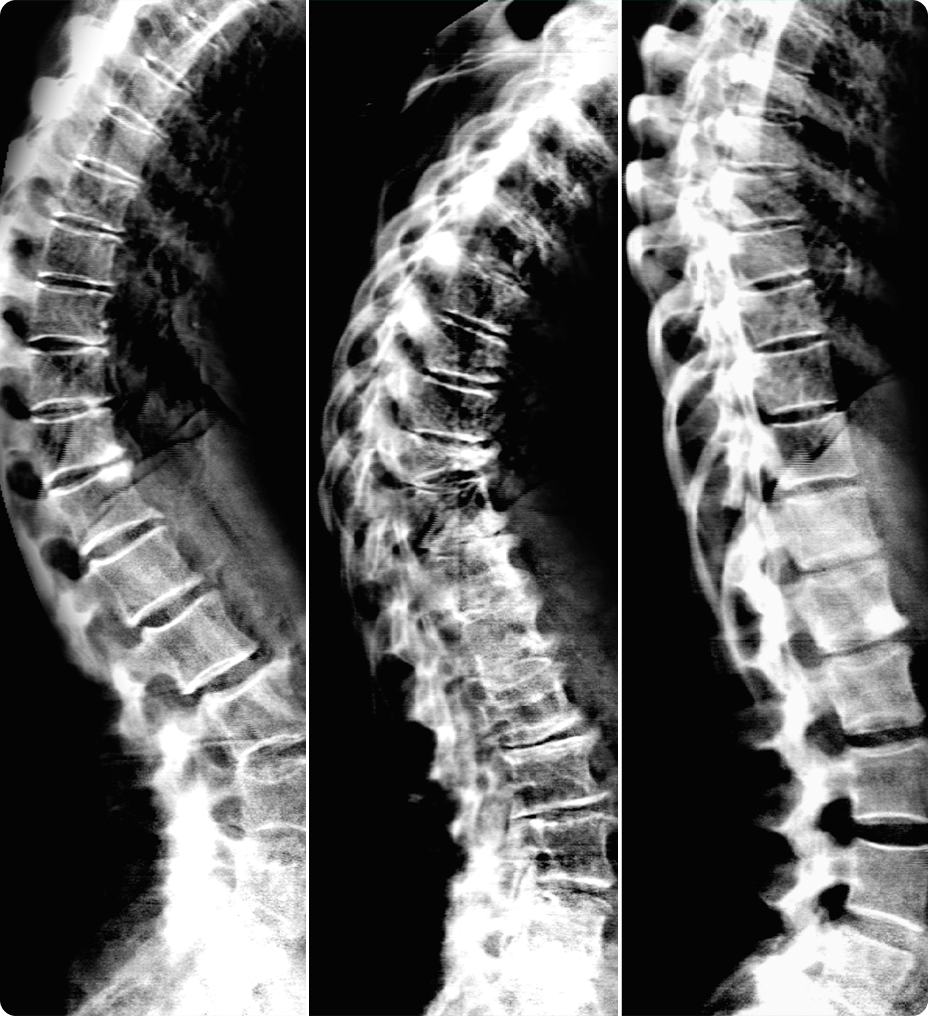

Nuestra cámara Xtream utiliza tecnología de detección precisa en tiempo real para generar un modelo 3D del cuerpo del paciente. A continuación, mediante nuestro algoritmo de aprendizaje profundo, Revolution Advance localiza el centro del rango de exploración y lo alinea automáticamente con el isocentro del túnel. Con un solo clic, el posicionamiento automático utiliza toda esta información para centrar automáticamente al paciente sin necesidad de intervención.

Esta tecnología inteligente proporciona tiempos de exploración más cortos, lo que hace que la experiencia de exploración sea más cómoda para sus pacientes. También ayuda a optimizar la dosis, mejora la calidad de la imagen y proporciona una mayor uniformidad en la exploración.